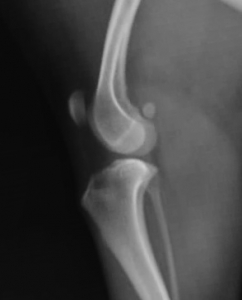

左下の写真がかなり重度の変形関節症を起こしている猫の膝関節のレントゲン写真です。赤い矢印で示したような関節症の進行に伴う関節鼠(ねずみ)(軟骨や骨のかけら)や骨棘(骨のでっぱり)が何か所も見られています。右が正常のものです。